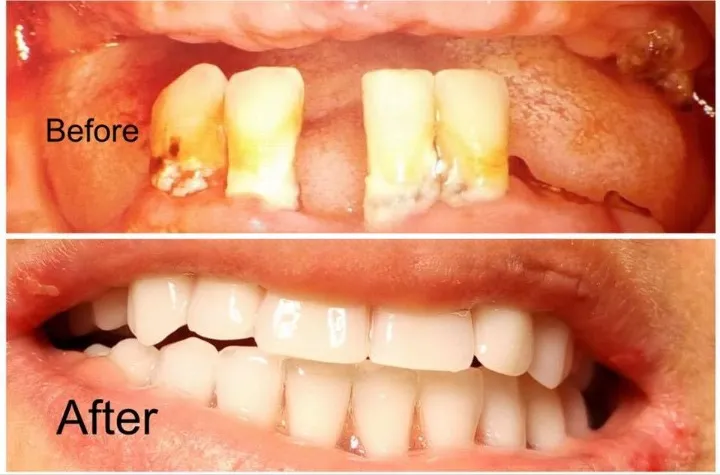

Greffes Gingivales

Corriger les récessions gingivales, renforcer les tissus fragiles et protéger les racines exposées.